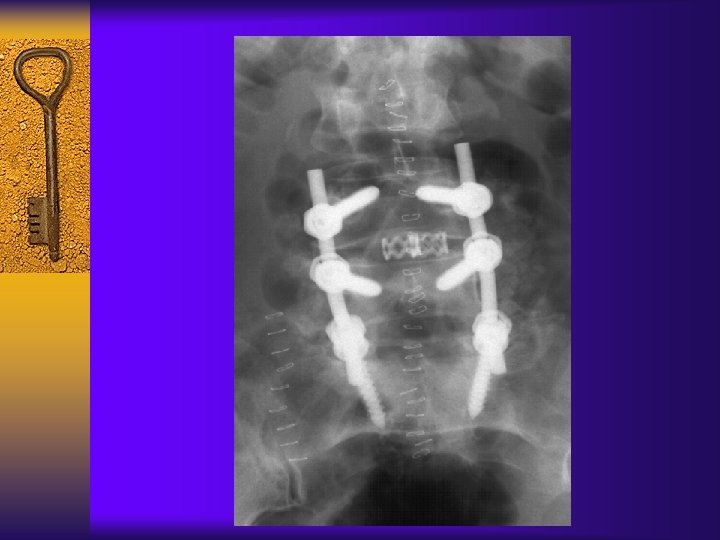

Surgical Treatment-Fusion 融 合 ¨ Instability – Spondylolisthesis – Scoliosis – Severe disc degeneration

Surgical Treatment-Fusion(融 合)

Decompression